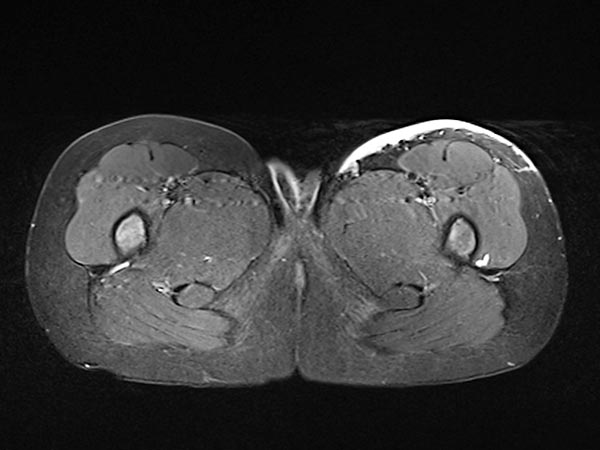

Axial, T2-weighted, fat-suppressed MRI of the patient at 7 years and 10 months of age.

The NICH is still visible under the skin as a hyperintense (white) flat structure, but significantly smaller than before embolization.